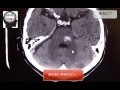

病気と症状について~「病気と症状いろいろナビ」. 病気にかかると、診断と治療は医師の手に委ねますが、自分の身体の今の情報を医師に伝えるのは自分自身です。. 橋出血のct画像診断【画像診断チャンネル】脳出血 youtube. Jun 26, 2014 救急画像診断を中心に、ct,mri画像診断、画像の読み方を解説しています。 xno1qq22cjlllou16giuj.Jp/. 効果減弱や副作用対策に有効な新癌疼痛治療薬:日経メディカル. 2017年6月19日、癌疼痛治療薬ヒドロモルフォン塩酸塩の即放製剤(商品名ナルラピド錠1mg、同錠2mg、同錠4mg)、徐放製剤. 橋出血のct画像診断【画像診断チャンネル】脳出血. · 脳卒中とは?(脳血管障害の基礎)【画像診断チャンネル】(脳出血、脳梗塞、クモ膜下出血) length 219. 画像診断. 脳出血は病名・原因・後遺症も場所によって違う 脳卒. 脳出血は大きなくくりで脳卒中に分類され、そこから脳出血や脳梗塞などに分けられ脳でおきる病気を全て 恐ろしい癌;